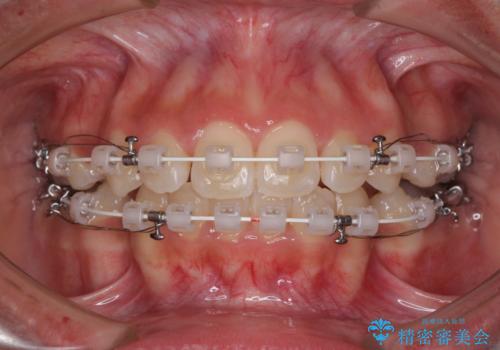

くちばしのように突出した前歯 口元を下げる抜歯矯正

- 上下の出っ歯を気にして来院された患者様です。

口元を積極的に引っ込めるために、上下左右の第一小臼歯を4本抜歯することとしました。

前歯部の突出と開咬は、舌突出癖によるものでしたので、舌のトレーニングをしっかりと行っていただき、1年半程度と短期間で治療を終えることができました。